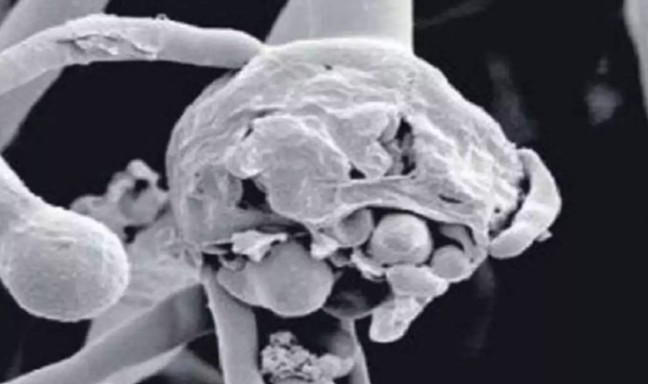

രാജ്യത്ത് ബ്ലാക്ക് ഫംഗസിന് പിന്നാലെ വൈറ്റ് ഫംഗസും സ്ഥിരീകരിച്ചു; കൂടുതൽ അപകടകാരിയെന്ന് ആരോഗ്യ വിദഗ്ദർ

ദില്ലി: കോവിഡ് വ്യാപനത്തിന്റെ രണ്ടാം തരംഗത്തിൽ ബ്ലാക്ക് ഫംഗസിസ് പിന്നാലെ വൈറ്റ് ഫംഗസും രാജ്യത്ത് സ്ഥിരീകരിച്ചിരിക്കുകയാണ്. ബ്ലാക്ക് ഫംഗസിനേക്കാൾ അപകടരമായ വൈറ്റ് ഫംഗസ് നാല് പേരിലാണ് ഇതുവരെ സ്ഥിരീകരിച്ചിരിക്കുന്നത്. ബിഹാറിലെ പാട്നയിലാണ് നാല് കേസുകളും റിപ്പോർട്ട് ചെയ്യപ്പെട്ടിരിക്കുന്നത്.

ആരോഗ്യ വിദഗ്ധരുടെ അഭിപ്രായത്തിൽ വൈറ്റ് ഫംഗസ് ബ്ലാക്ക് ഫംഗസിനേക്കാൾ അപകടകരമാണ്. ഇത് ഇത് ശ്വാസകോശത്തെയും ശരീരത്തിന്റെ മറ്റ് ഭാഗങ്ങളെയും നഖങ്ങൾ, ചർമ്മം, ആമാശയം, വൃക്ക, തലച്ചോറ്, സ്വകാര്യ ഭാഗങ്ങൾ, വായ എന്നിവയെയും ബാധിക്കുന്ന രോഗമാണ്. ശ്വാസകോശത്തെ ബാധിക്കുന്നതുകൊണ്ട് തന്നെ കോവിഡ് പോലെ തന്നെ സമാനമായ അണുബാധയാണ്. നേരത്തെ രോഗികളുടെ എണ്ണവും കൂടുന്ന സാഹചര്യത്തിൽ ബ്ലാക്ക് ഫംഗസിനെ സാംക്രമിക രോഗങ്ങളുടെ പട്ടികയിൽ ഉൾപ്പെടുത്താൻ കേന്ദ്ര ആരോഗ്യ മന്ത്രാലയം സംസ്ഥാനങ്ങൾക്ക് നിർദേശം നൽകി.